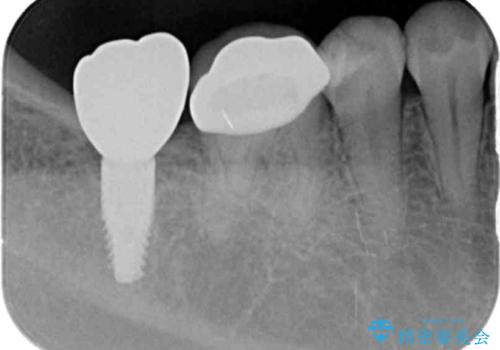

奥歯のインプラント治療

- 右下の奥歯を虫歯で喪失しそれ以来よく物が噛めず、改善を求めて来院されました。

入れ歯かインプラント治療のご提案を行い、よりしっかりとかめるインプラント治療を希望されました。

骨との結合する期間が早く、大きな咬合力にもしっかりと耐えることのできるストローマンインプラントを用いた咬合機能回復を計画します。

- 44万円(ストローマンインプラント・チタンカスタムアバットメント・仮歯・フルジルコニアクラウン)費用は治療当時の料金となります